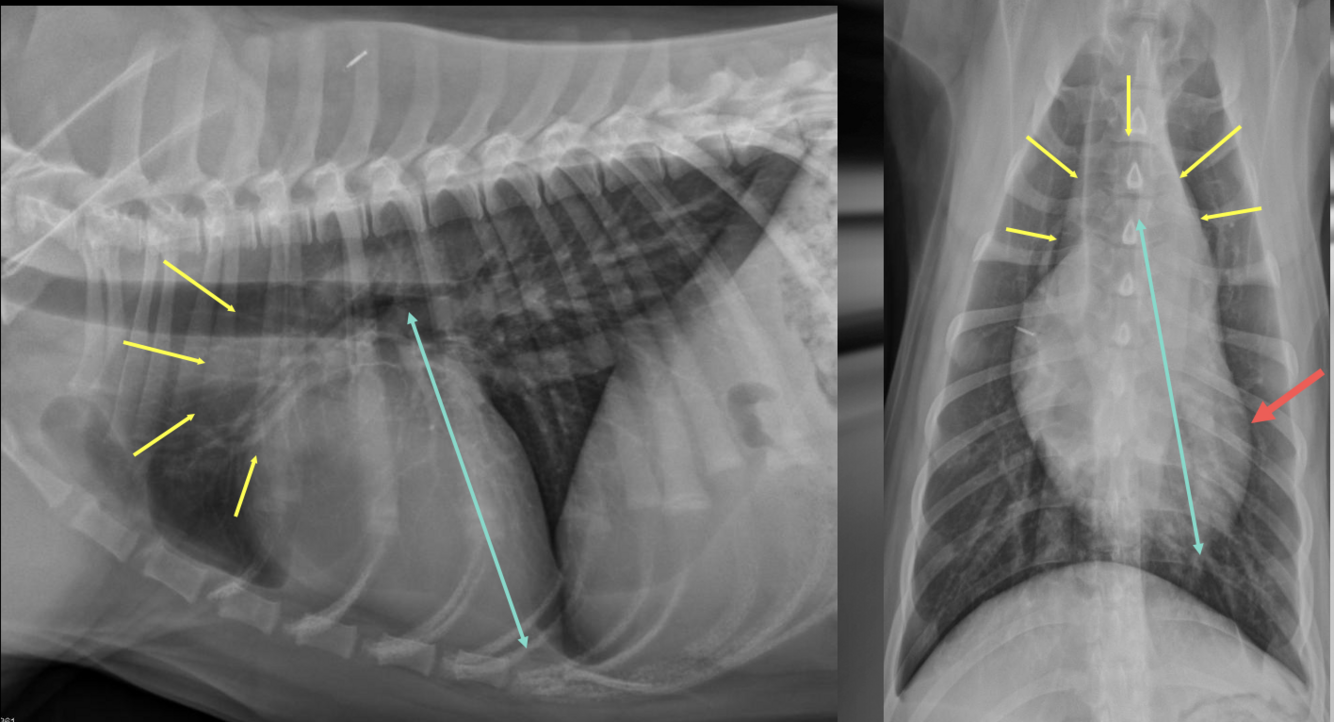

What is shown in these images?

peritoneo-pericardial diaphragmatic hernia

What are the radiographic findings in peritoneal-pericardial diaphragmatic hernia?

-enlarged, globoid or abnormally shaped cardiac silhouette -silhouetting of cardiac silhouette and diaphragm -may see gas-filled bowel loops or fat in chest -possible "empty abdomen"/missing abdominal organs or small liver -possible concurrent sternal anomaly